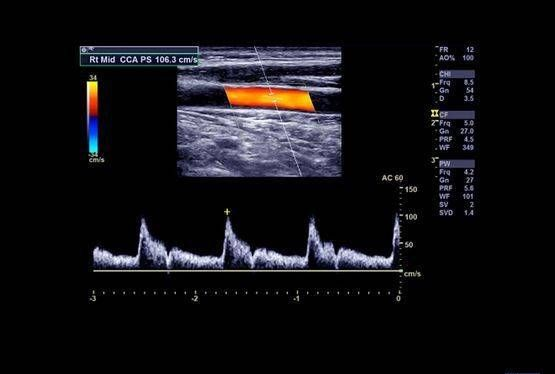

Nous réalisons également des échos Doppler des artères (carotides, aorte, membres) et des veines, notamment pour le bilan de phlébite ou la recherche de thrombose. Nous ne pratiquons pas d’échographies cardiaques ni de grossesse.